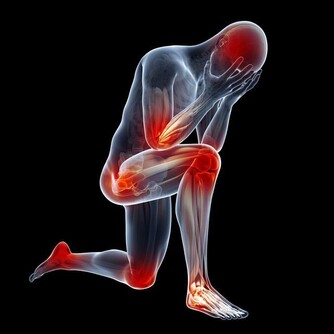

建議大家可以壓壓看自己的左下腹部,

如果是硬硬脹脹的,很可能就是有宿便積在裡面,

這時如果做咖啡灌腸,就會發現它變柔軟了。

有些人在用力排便時,腸子因為壓力的關係,

讓結腸壁較脆弱的地方像吹氣球一樣

長出一個氣囊出來,就形成了憩室。

它是一種良性的囊袋,是大腸最容易藏汙納垢的地方,

如果不處理,久而久之就有形成大腸癌的可能。

憩室一旦長出來就不易消除,

老人家和便秘者有百分之三十到四十的人都會有憩室,

平時不痛不癢,就像盲腸一樣,

如果沒有髒東西跑進去就沒事,

但如果排泄物囤積其中,就容易發生感染或發炎。